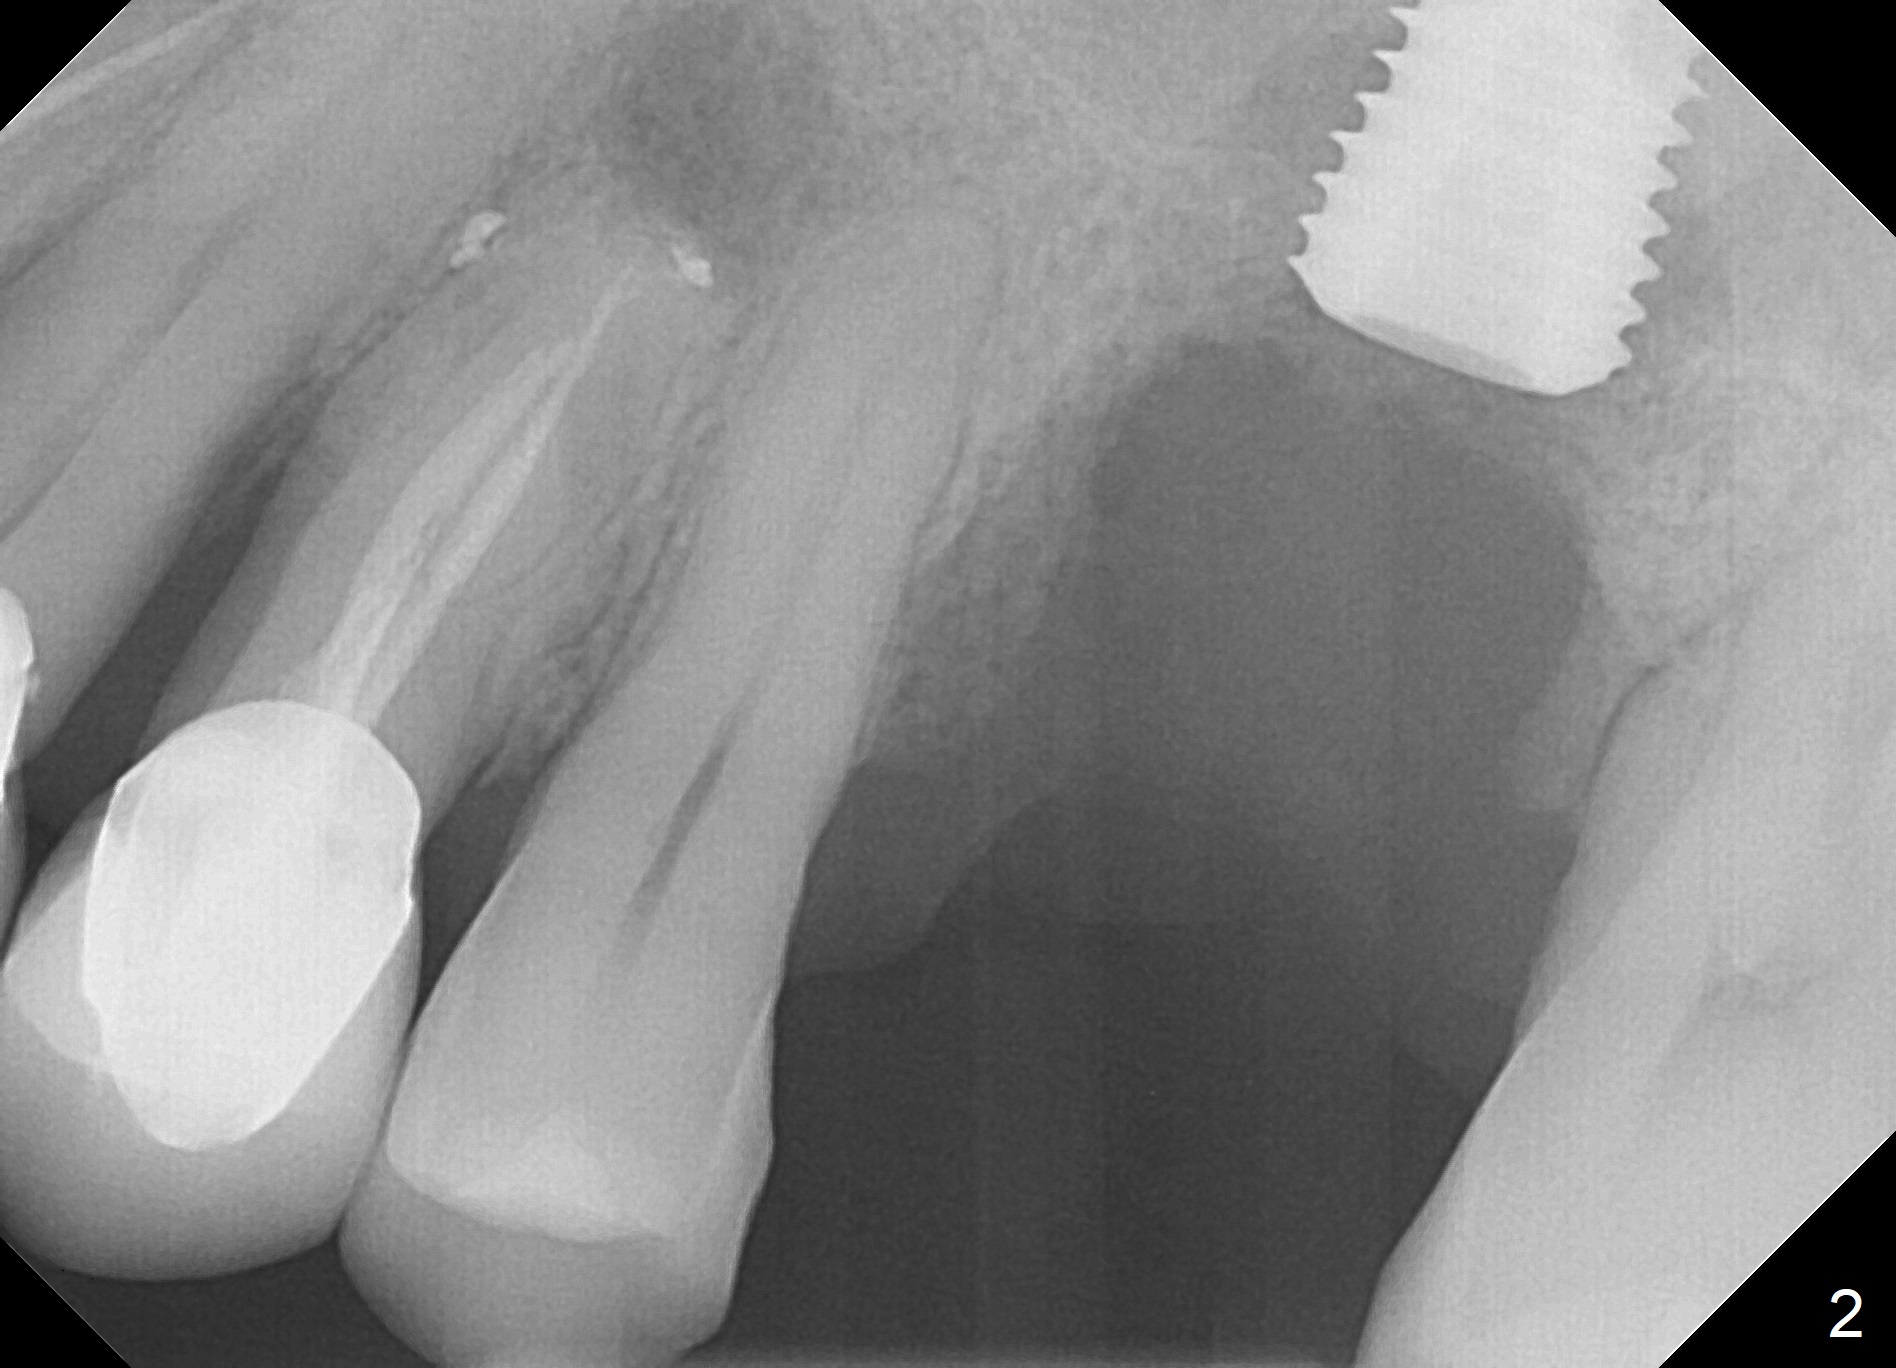

When the tooth #14 is extracted, the buccal plate is lost, while the apex of the palatal socket is perforated.  The palatal slope of the septum appears to be a suitable site for osteotomy, but the depth seems to be 2 mm.  After sequential osteotomy until 5.3 mm with drills, a 5.9 mm SM tap obtains stability (Fig.2).  A 5.9x8 mmm implant is placed with barely sufficient stability after 1 piece of PRF membrane and VeraGraft (Fig.2-4).  The implant rotates and dislodges when an abutment is being placed.  Neither do 6-8x17 mm Tatum taps achieve primary stability.  Socket preservation is performed, followed by periodontal dressing (Fig.5).  Primary stability might have been obtained if a smaller IBS implant with fins were placed in the palatal socket.  The periodontal dressing has dislodged 1 week postop; the socket appears healing (Fig.6,7).  Bone graft seems to be minimal or bone density of the graft is low (Fig.8).  The socket heals with a wide ridge 2 months post socket preservation, but the tooth #15 seems to be buccal (Fig.9) and mesial (Fig.10) shift.  After use of Magic Split and Expanders (until 3.8 mm for 13 mm), try 5 mm dummy implant (Fig.11).  If 6 mm one fails to achieve stability substantially, switch to 7 mm Tatum tapered tap provided there is enough mesiodistal space (use 8 mm implant positioner to gauze the space beforehand (preop)).  Consider using Vanilla (not Vera) Graft to fill in the gap between implant and osteotomy.  When primary stability is obtained, place a nonfunctional provisional to prevent further shifting (Fig.11 white outline).  After osteointegration, use the provisional (reline and separator) to distalize the tooth #15.